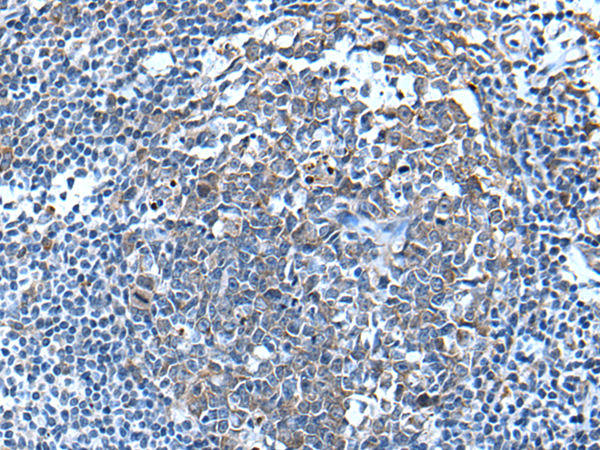

分类: 科研抗体货号: P05945别名: CFND; CFNS; EFB1; EFL3; EPLG2; Elk-L; LERK2应用: IHC反应种属: Human, Mouse, Rat